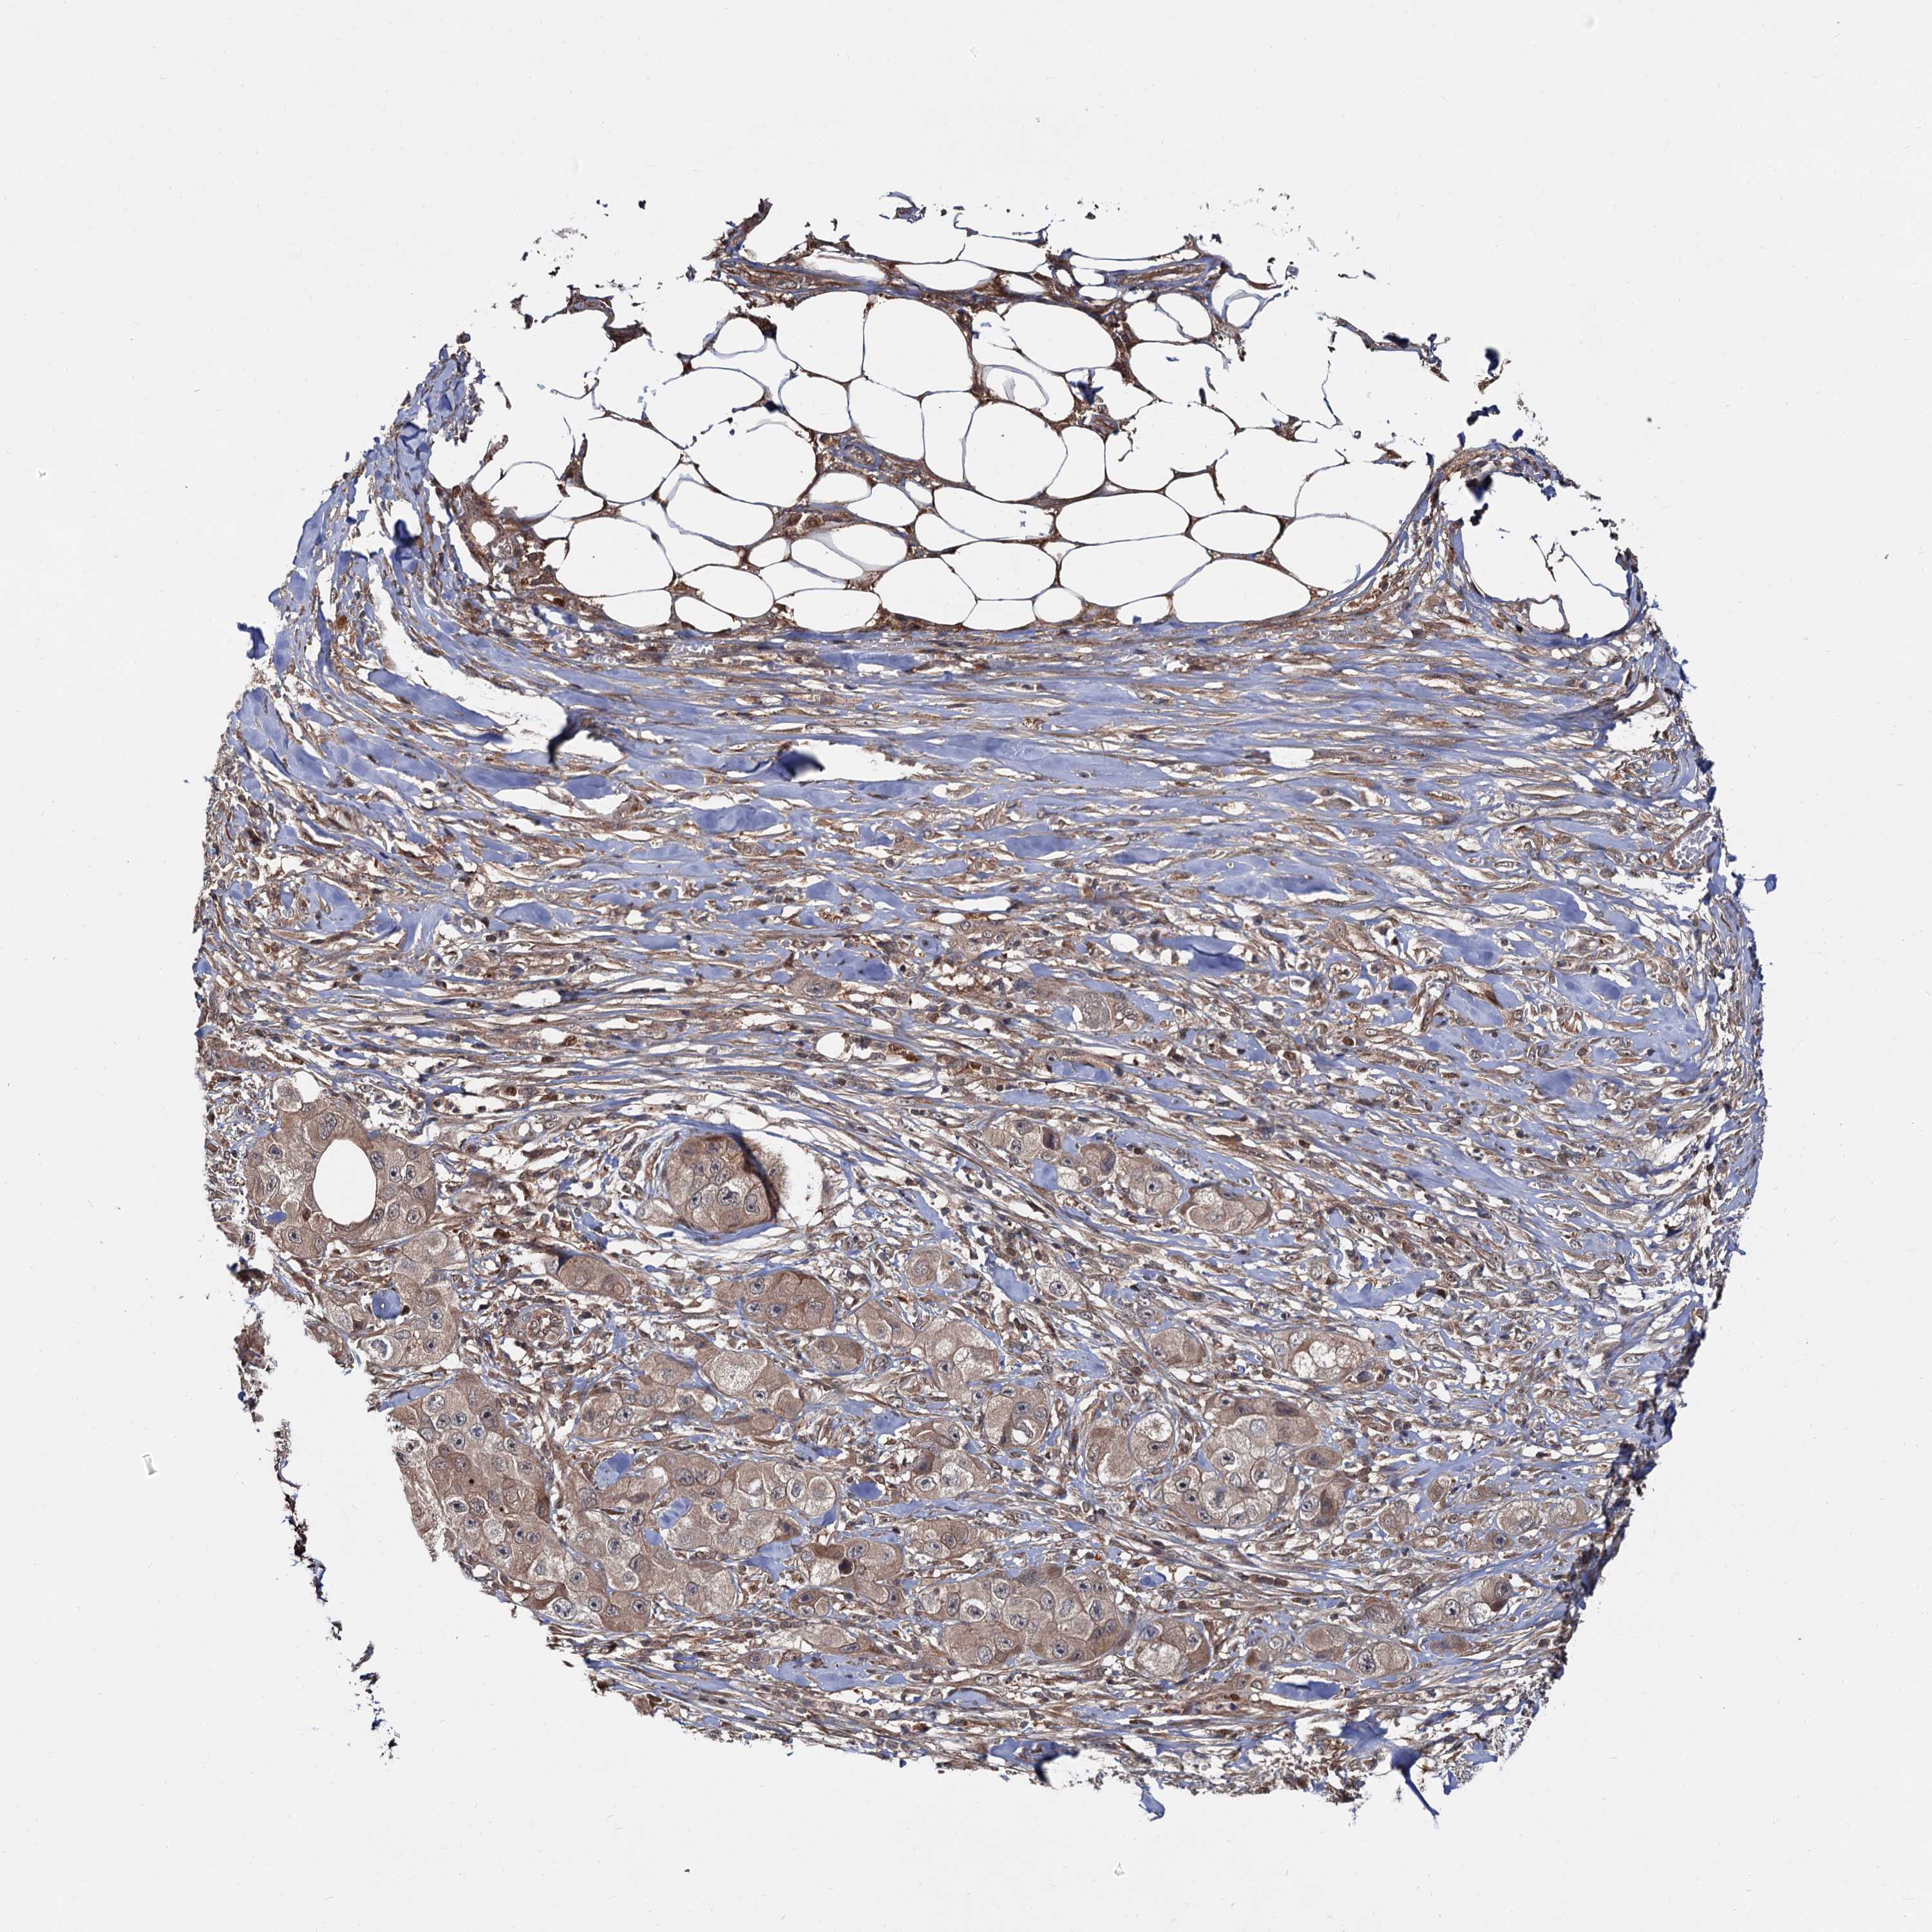

SKIN CANCER - Protein expressioni

A mouse-over function shows sample information and annotation data. Click on an image to view it in a full screen mode. Samples can be filtered based on level of antibody staining by selecting one or several of the following categories: high, medium, low and not detected. The assay and annotation is described here.

Antibody stainingi

Antibody staining in the annotated cell types in the current human tissue is reported as not detected, low, medium, or high, based on conventional immunohistochemistry profiling in selected tissues. This score is based on the combination of the staining intensity and fraction of stained cells.

Each image is clickable and will lead to virtual microscopy that enables deeper exploration of all samples and also displays staining intensity scores, fraction scores and subcellular localization as well as patient and tissue information for each sample.

Antibody HPA036287

Staining

High

Intensity

Strong

Quantity

>75%

Location

Cytoplasmic/membranous

Squamous cell carcinoma, metastatic, NOS